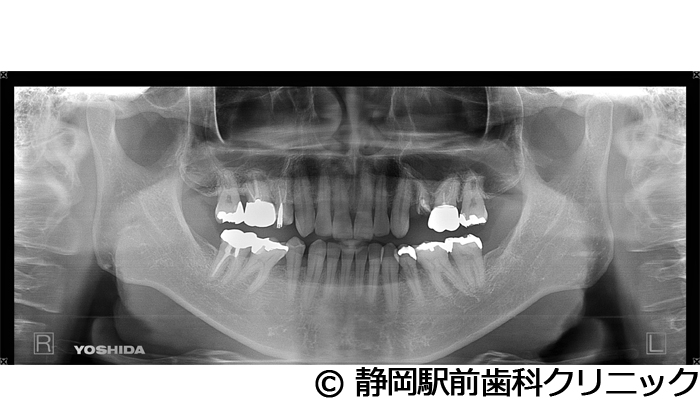

【症例1】左上インプラント埋入

- 治療前

- 治療後

- 治療名

- 左上インプラント埋入

- 費用

- 330,000円(税込)

- 期間

- 6ヵ月

治療内容

患者様の症状

左上の歯が歯根破折で、被せ物が土台から取れてしまった。インプラント治療希望。

治療方法

残った歯の抜歯を行い、骨の治癒後にCTを撮影。精密に診断後、インプラントを埋入した。ソケットリフトを併用し、インプラントの埋入範囲も確保しながら行った。その後、人工歯を被せて咬合と審美の両方を構築した。

治療結果

術後はほぼ痛みがなく、短期間で噛むことができるようになったとご満足いただけました。見た目も自分の歯のようだと喜んでいただけました。

※治療結果は個人差があります。

治療を行う上での注意点(リスク・副作用)

術後は、出血、腫れ、痛みなどが出る可能性があります。